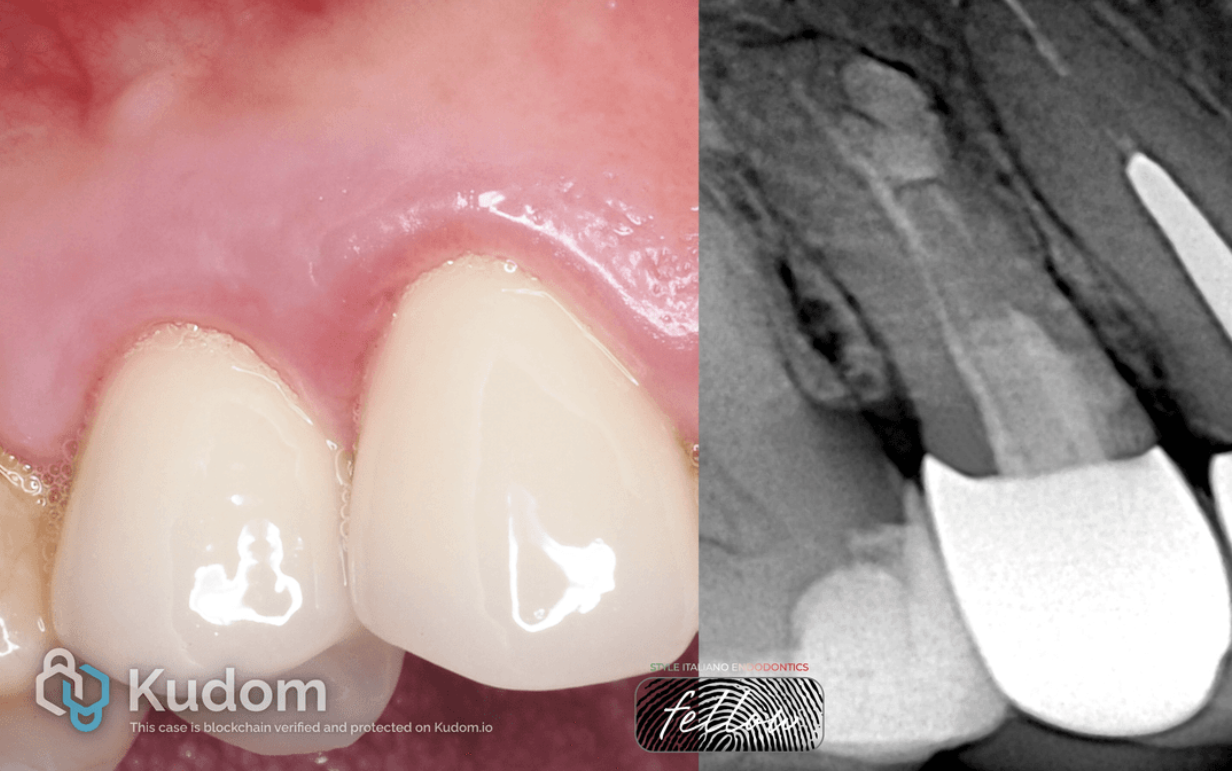

Fig. 2

The figure shows incorrect treatment protocol planning and very aggressive root canal preparation for metal intraradicular posts, which subsequently led to a root perforation in the apical portion